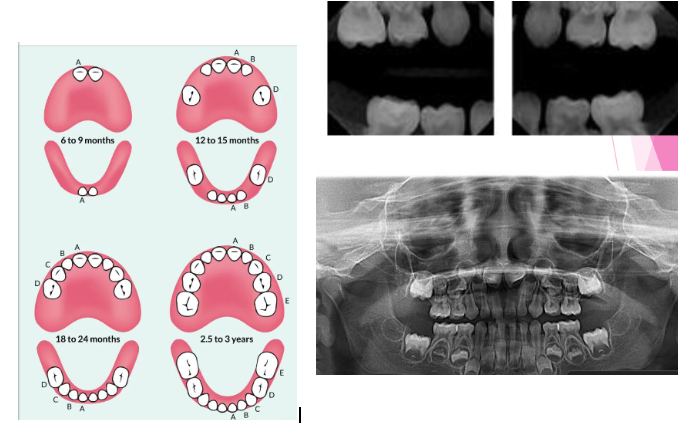

Primary Dentition Stage

knowt flashcard image

Mixed dentition stage

Permanent dentition stage

Tooth eruption sequence

Eruption sequence (permanent teeth)